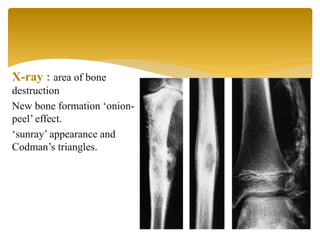

X-ray : area of bone

destruction

New bone formation ‘onion-

peel’ effect.

‘sunray’ appearance and

Codman’s triangles.